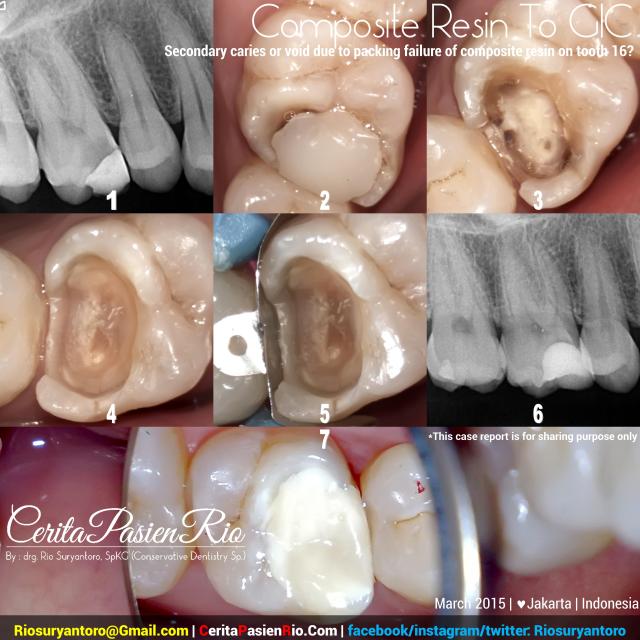

Picture Information:

1. x-rays image showing an undemined caries in tooth 16 (upper right first molar), there was a big composite filling which loss its retention (fig. 2). the cavity had almost reached the pulp (from the x-ray image).

2. the composite resin appearance, showed a leakage across the marginal line, and a loss of retention, the proximal contact was bad. the previous operator might not be able to pack the composite well, and might not use a propriate proximal matrix.

3. I remove the restoration, and saw many demineralized dentin underneath the restoration.

4. all the infected dentine already removed, and ready to receive a restoration. in here, i checked the tooth vitality once more to make sure the pulpal status. and yup, the pulp was still vital, the dentin was still intact. but, i am not so sure about my diagnosis, so i put GIC rather than composite resin, as an intermediate restoration, until i got a proper diagnosis.

5. I put a sectional matrix, checked the tightness of the edge of the gingival wall and the matrix band. i used palodent plus from Dentsply.

6 and 7. finished glass ionomer placement, and x-ray evaluation showed that all the GIC had been packed well to adapt with cavity margin.

I restored the cavity using glass ionomer cement (Ketac Molar, 3M ESPE), the matrix i used was Palodent Plus. the time lapse was 30 minutes including a polishing and finishing time.